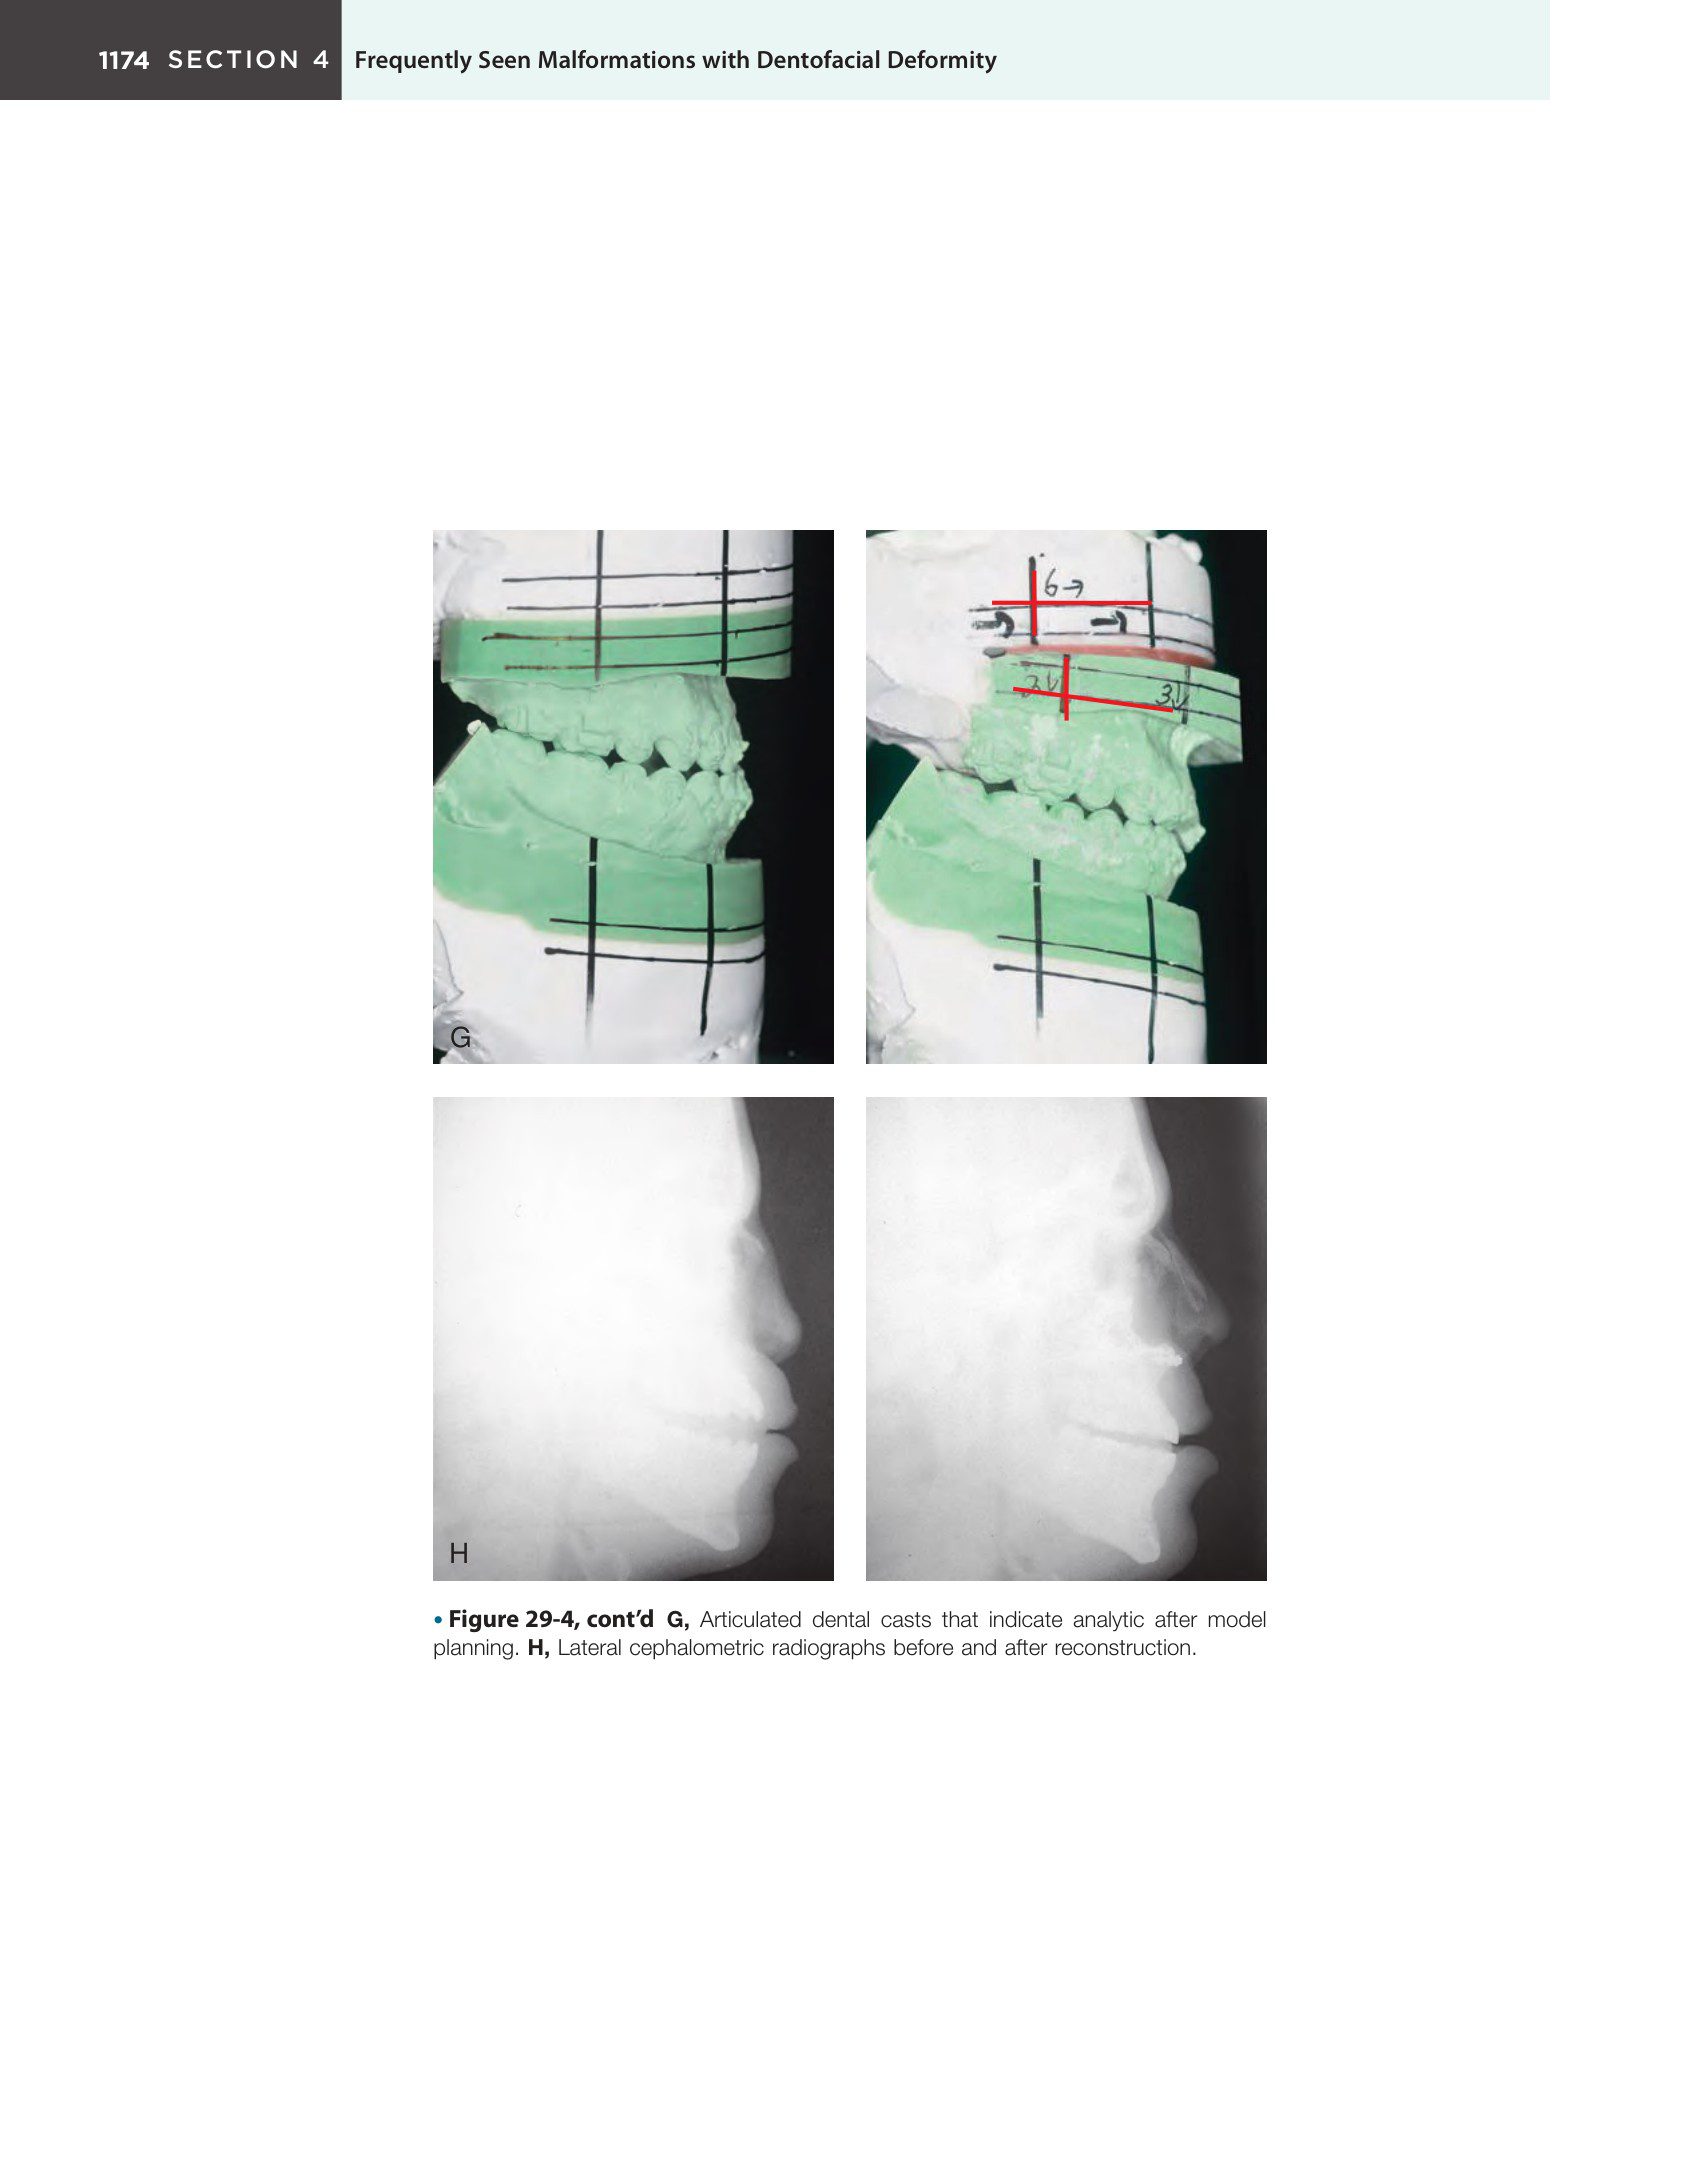

- Kỹ thuật phẫu thuật: Các phương pháp can thiệp như cắt xương hàm trên (Le Fort I, II), ghép xương, và tái tạo mũi bằng sụn sườn hoặc xương sọ để cải thiện hình dáng mũi và độ nhô của tầng giữa mặt.